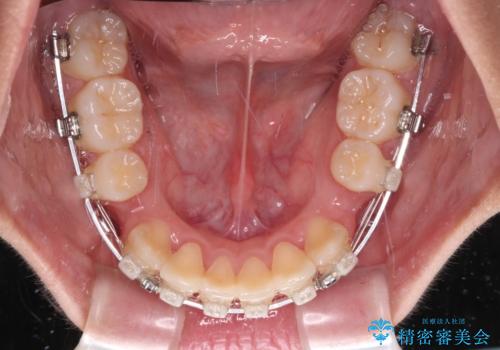

- 矯正装置

- クリアブラケット

- 2年9ヶ月

- 治療回数

- 30回以上